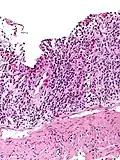

Цитомегаловірус (ЦМВ, ГВЛ-5, Cytomegalovirus hominis) належить до роду Cytomegalovirus, підродини Betaherpesvirinae, родини Herpesviridae. ЦМВ має найбільший геном серед людських герпесвірусів. Наразі відомо троє серотипів цитомегаловірусу людини I, II, III, до яких відносять багато штамів: AD-169, Davis, Towne, TB40/E, Toledo, Merlin, 3157, 6397, 711, 5234, що, можливо, і призводить до різного потенціалу захворюваності[10]. ЦМВ добре зберігається при кімнатній температурі, чутливий до дезрозчинів та нагрівання. ЦМВ зростає в лабораторних умовах лише в культурі людських клітин і, найкраще, в культурі фібробластів. ЦМВ (як й інші β-герпесвіруси) здатні спричиняти характерний феномен цитомегалії — велике збільшення клітин у розмірах із включенням в ядра самих вірусів у вигляді «ока сови».

При локалізованих формах захворювання гігантські клітини знаходять, як правило, в слинних залозах (переважно в привушних залозах, рідше в підщелепних і під'язикових). Формування цитомегалії відмічають в епітелії слинних вивідних проток. В стромі, що їх оточує, відзначають клітинні лімфогістіоплазматичні інфільтрати.